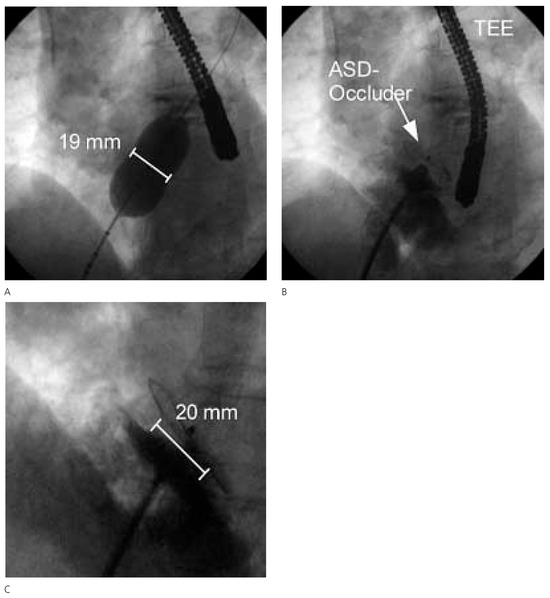

In der transthorakalen Echokardiographie fand sich eine linksventrikuläre Hypertrophie bei normaler systolischer Funktion. Zusätzlich bestand eine minime Mitralinsuffizienz und Aorteninsuffizienz. Es fand sich ein Vorhofseptumaneurysma mit einem kleinen Shunt auf Vorhofebene (Figure 1). Der pulmonal-arterielle Druck war entsprechend dem Doppler-echokardiographisch erhobenen Druckgradienten zwischen rechtem Ventrikel und rechtem Vorhof (30 mm Hg) nicht erhöht. In der anschliessenden transösophagealen Echokardiographie (Figure 2) konnte ein ASD Typ II im Bereich des Foramen ovale mit einem bidirektionalen Shunt, einem Vorhofseptumaneurysma und einer persistierenden Eustach-Klappe dargestellt werden.

Figure 1.

Echokardiographie mit Vorhofseptumaneurysma.